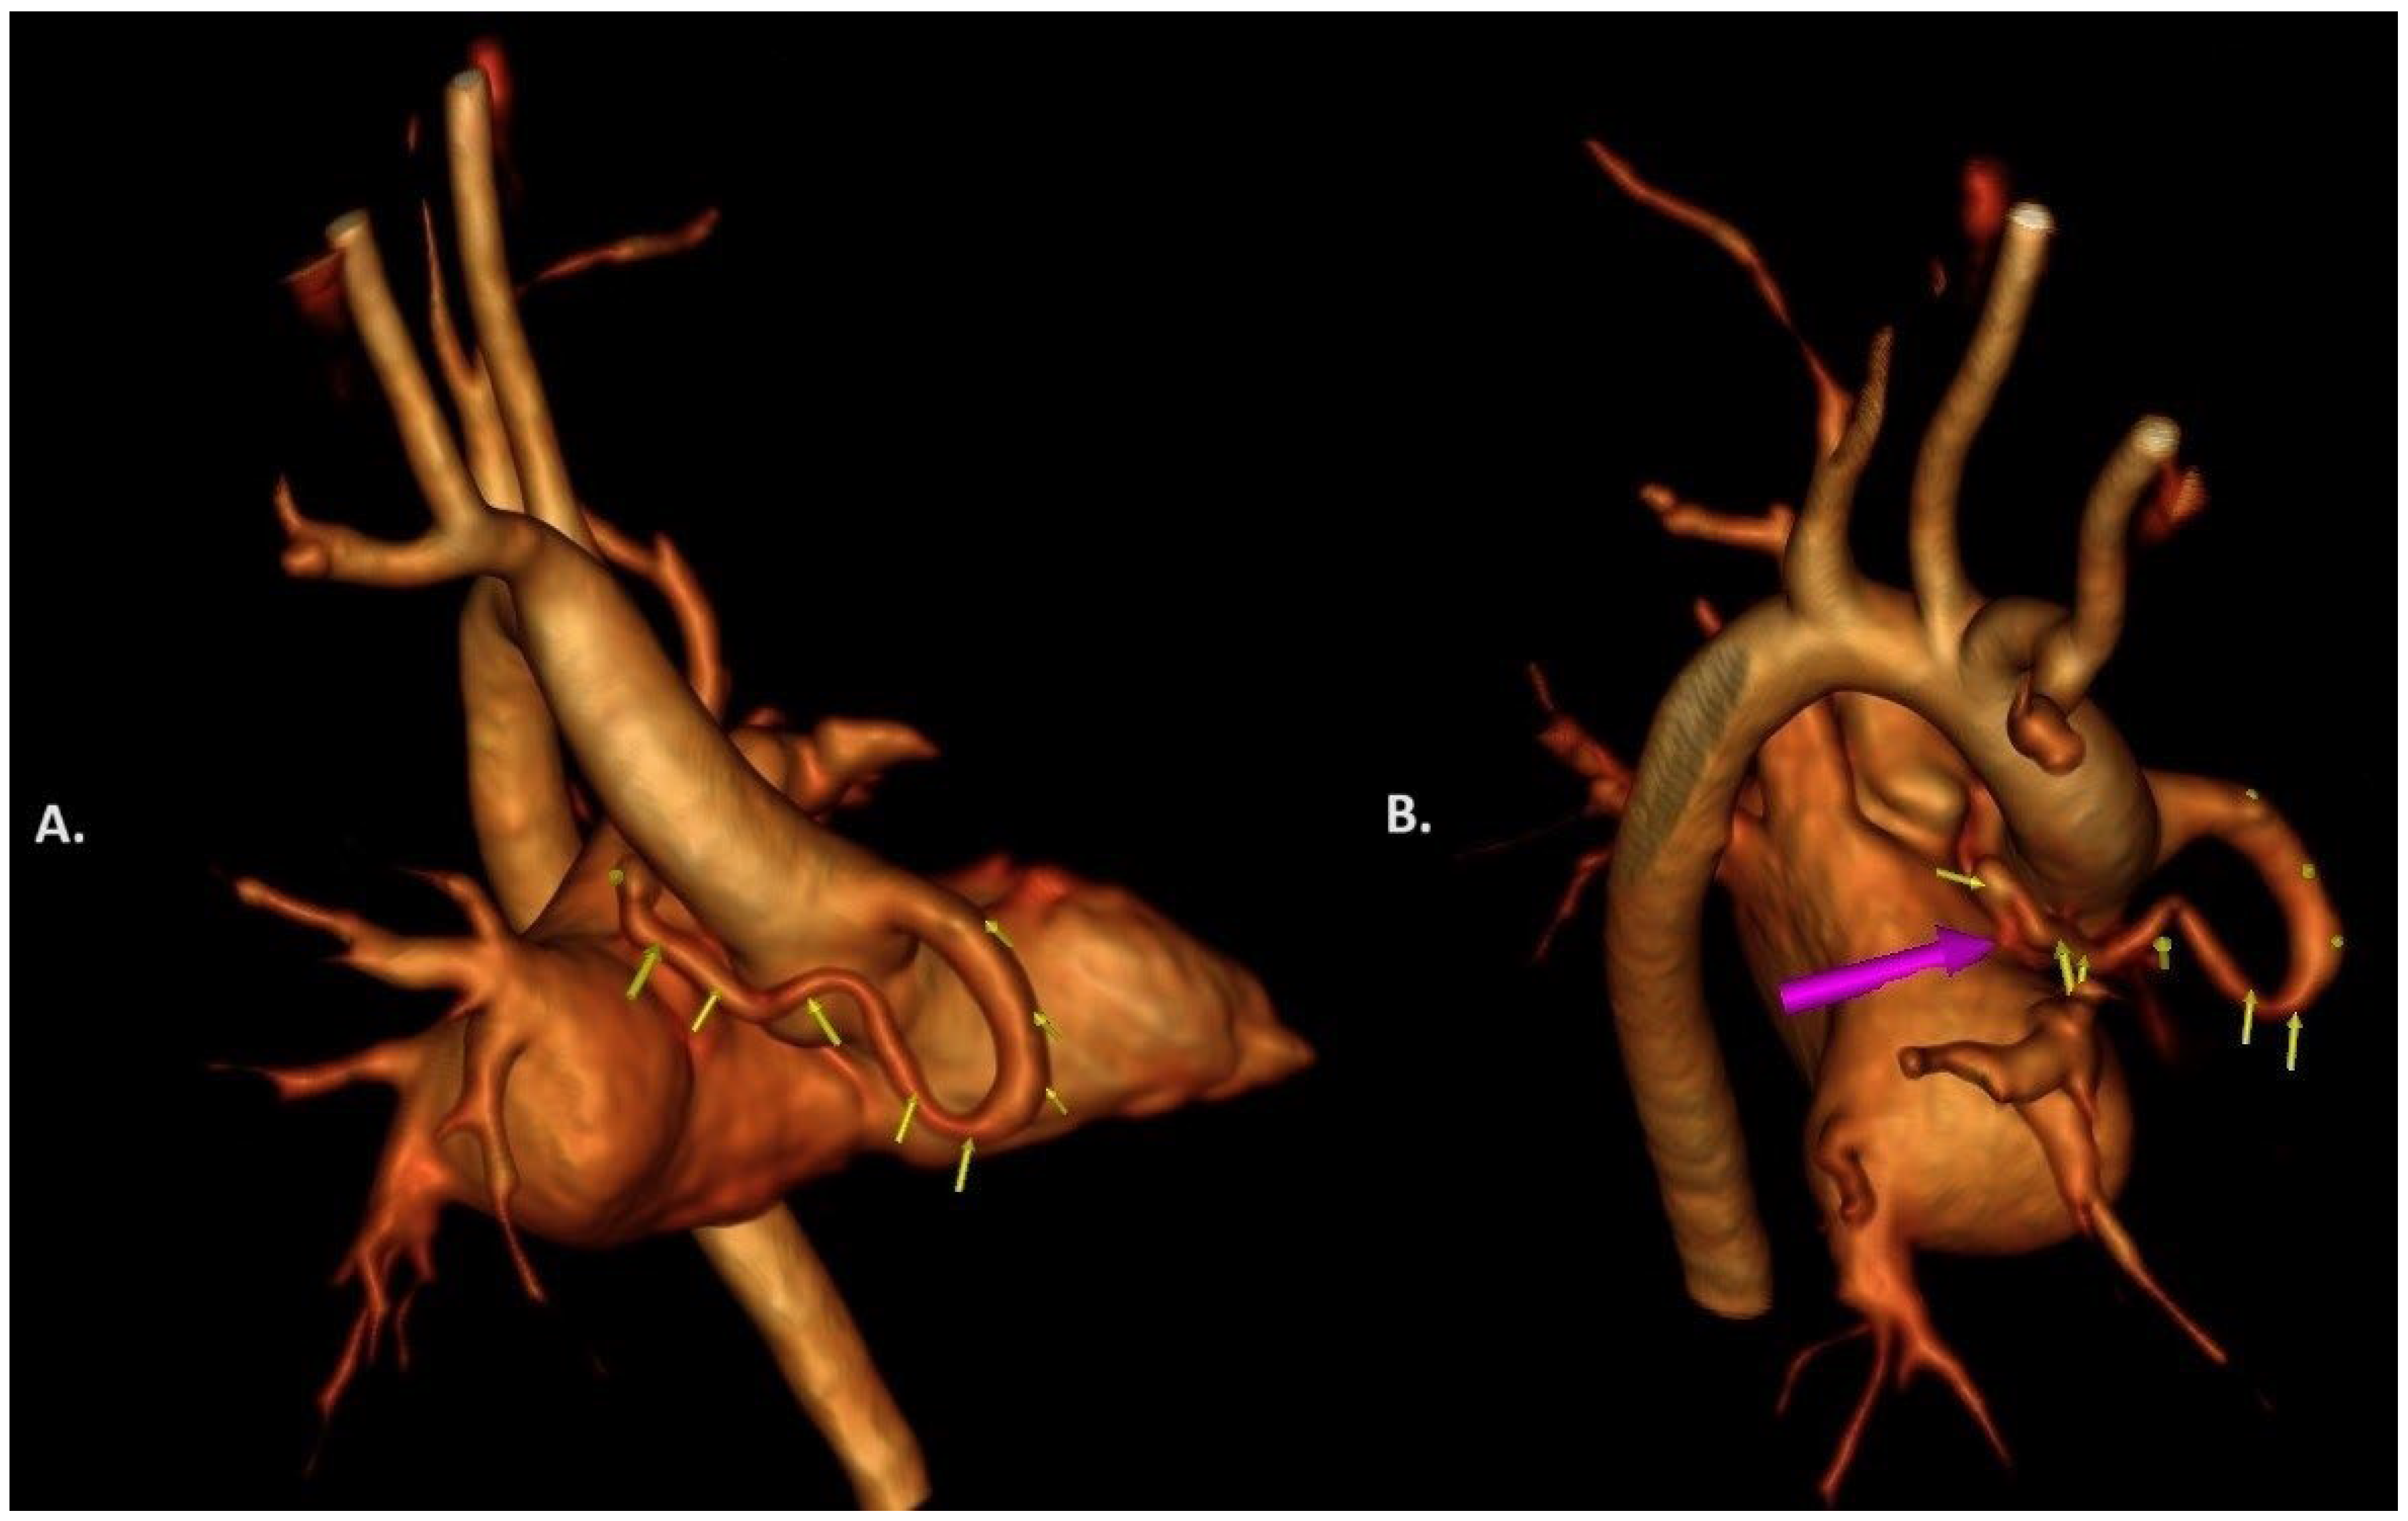

2. Case Report